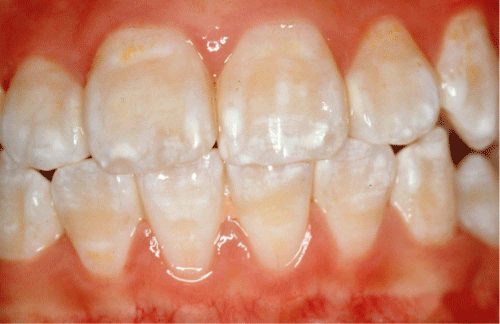

Các biểu hiện chủ yếu của bệnh như sau:

– Bề mặt răng biến đổi màu, xuất hiện các đốm màu trắng mờ đục. Với mức độ thiếu sản men răng khác nhau đốm màu này tăng dần sắc độ từ trắng, vàng trắng cho đến nâu

– Men răng bị đổi màu sang nâu nhẹ và có các vệt lõm trên bề mặt thân răng

Dấu hiệu của thiếu sản men răng